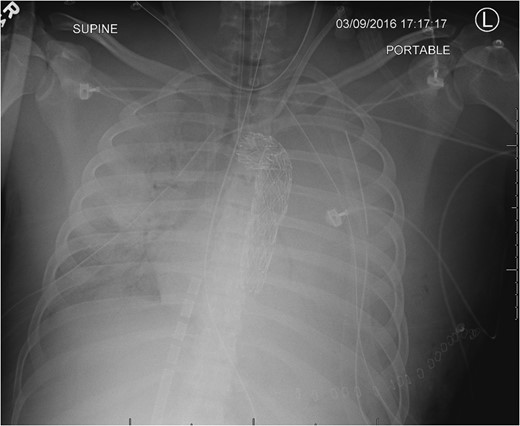

Admission AP CXR demonstrating a widened mediastinum and increased haziness of the left hemi-thorax.